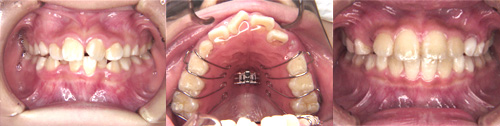

◇ 実際の治療 実際に当クリニックで治療を終了された患者さんの写真を、許可を得て掲載しております。 費用について- 【相談料】 無料